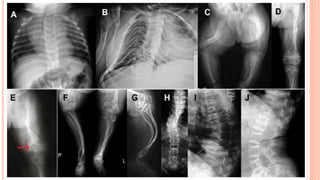

 Radiographs

 Generalized osteopenia

 Thinning of long bone

 Fracture in various stages of healing

 Vertebral compression

 Spinal deformity

 Widening of metaphysis

 Popcorn epiphysis

INVESTIGATIONS  Radiographs  Generalizedosteopenia  Thinning of long bone  Fracture in various stages of healing  Vertebral compression  Spinal deformity  Widening of metaphysis  Popcorn epiphysis